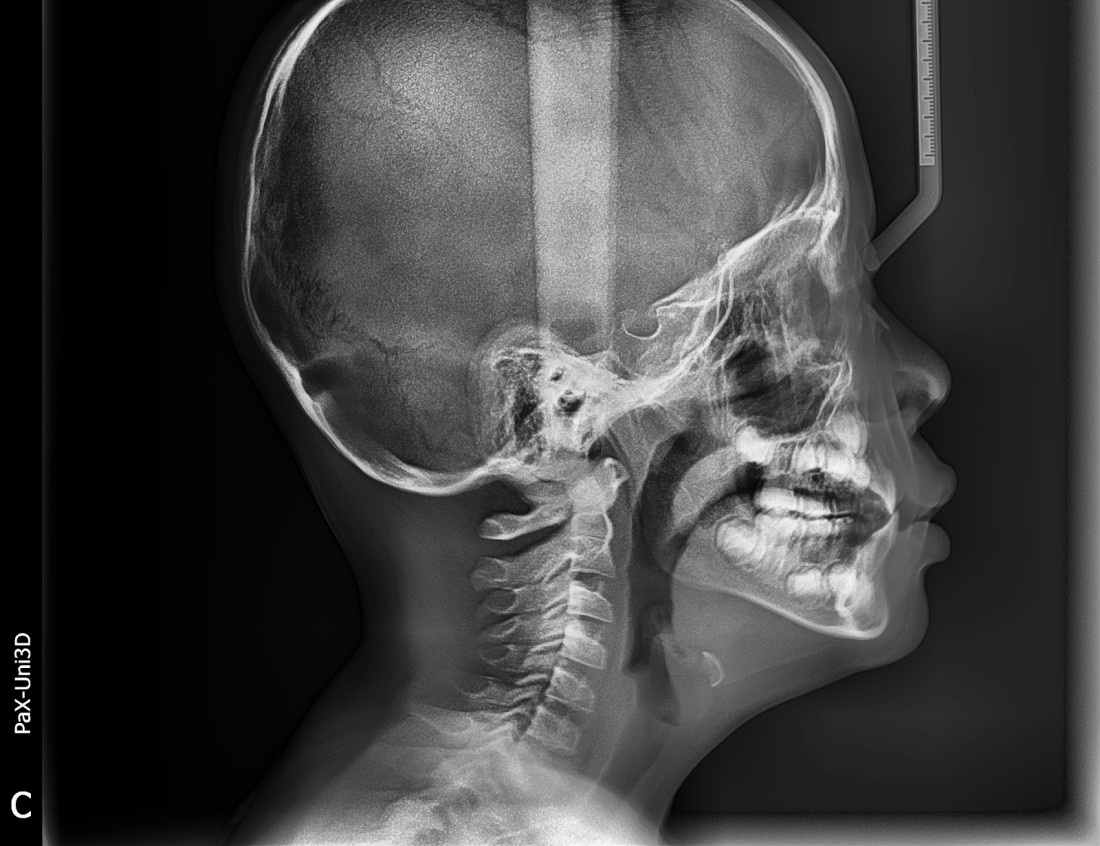

演示图片2

精确识别头颅侧位片中17个关键解剖标志点